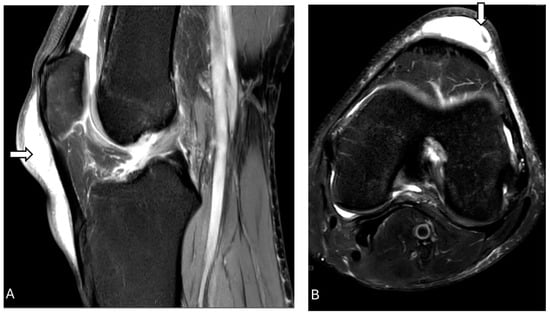

3.9. Osteomyletis of Patella